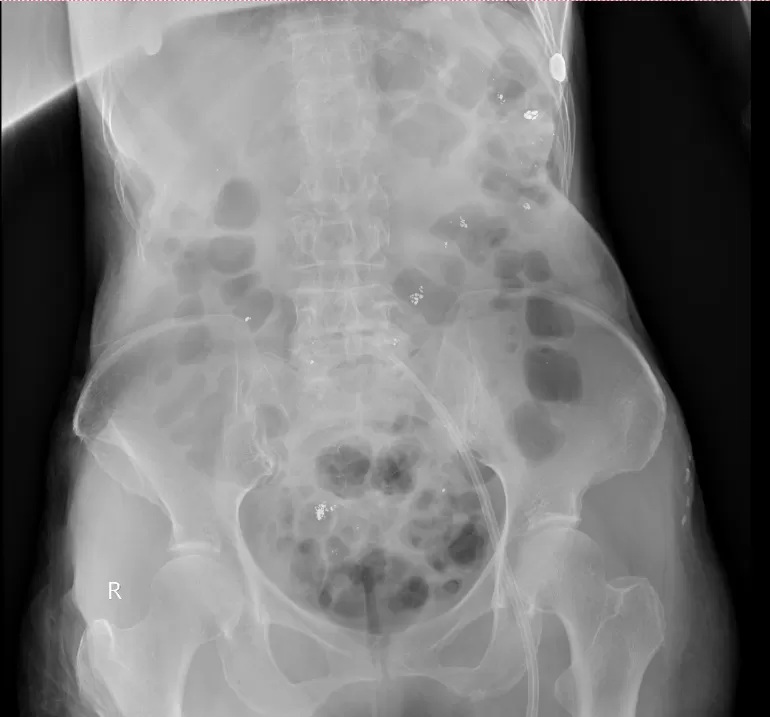

d2.webp 腹平片可以看到患者消化道内残留大量汞

入院当天,姜阿婆尿汞浓度高达73465.47μg/L(肌酐校正),比正常值高1万8千多倍;反映肾功能的肌酐清除率仅有6.21ml/min,出现无尿,提示已存在肾功能衰竭;转氨酶、心肌酶升高,肝脏、心肌均出现了不同程度的损害。